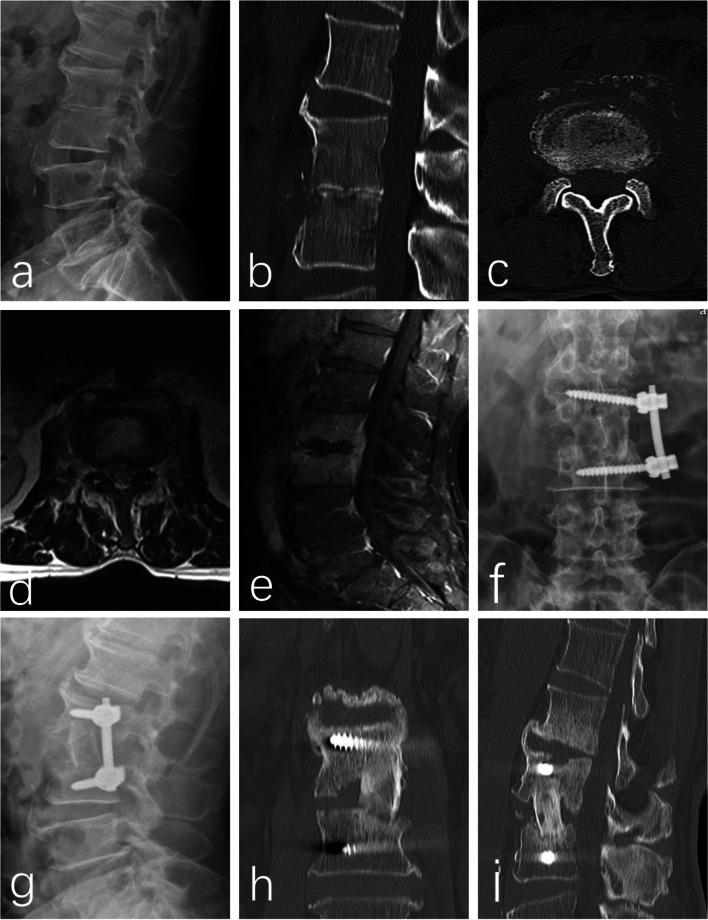

The aim of the present study was to investigate the efficacy and safety of mini-open oblique debridement and lumbar interbody fusion combined with lateral screw fixation for treating single-level pyogenic spondylodiscitis.

Twelve patients with single-level lumbar pyogenic spondylodiscitis underwent OLIF combined with lateral screw fixation were analyzed. Patients underwent follow-up for 12 to 24 months. The clinical characteristics, etiological examinations, operative time, intraoperative blood loss, Oswestry Disability Index (ODI), visual analog scale score (VAS), postoperative complications, and the bony fusion rate were recorded.

RESULTS

The mean follow-up period of time was 14.8 months. The average operative time and intra-operative blood loss were 129.0 ± 19.76 min and 309.2 ± 92.96 mL, respectively. No severe intra-operative complications were observed during surgery, except in 1 case that develops abdominal pain and distension after surgery, 2 cases that develop left-sided transient thigh pain/numbness and 8 cases that complains of donor site (iliac crest) pain. All of these symptoms disappeared 8 weeks after surgery. Tissue sample cultures were obtained from all patients intraoperatively and four (33.3%) were positive, including 2 with Staphylococcus aureus, 1 with Staphylococcus epidermidis, and 1 with Escherichia coli. During an average of 22.5 ± 2.1 days (range, 14-29 days) after surgery, WBC, CPR, and ESR levels in all patients had returned to normal. All patients were pain free with no recurring infection. Solid bony fusions were observed in all cases within 6 months, including 10 with I grade fusion, 2 with II grade fusion according to the classification suggested by Burkus et al. No fixation failure was observed during follow up and solid bony fusions were observed in all 12 patients at finally follow-up. A significant postoperative increase was also observed in the mean segmental height and lordosis (P < 0.05), followed by a slight decrease of segmental height and lordosis at final follow-up. At the final follow up, the mean VAS (1.5 ± 0.6) and ODI (18.9 ± 7.6) were significantly lower than VAS (8.4 ± 2.7) and ODI (71.2 ± 16.5) before surgery (P < 0.01).

Single-stage debridement with autogenous iliac bone graft through the OLIF corridor and lateral fixation was a feasible surgical approach in our consecutive 12 cases of pyogenic spondylitis.